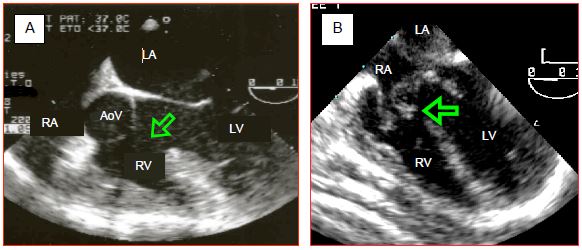

For further information, reference may be made to Chapter 14 (Paediatric cardiac surgery). Illustrations are taken from transesophageal echocardiography (TEE), which anaesthetists may perform in the operating theatre.